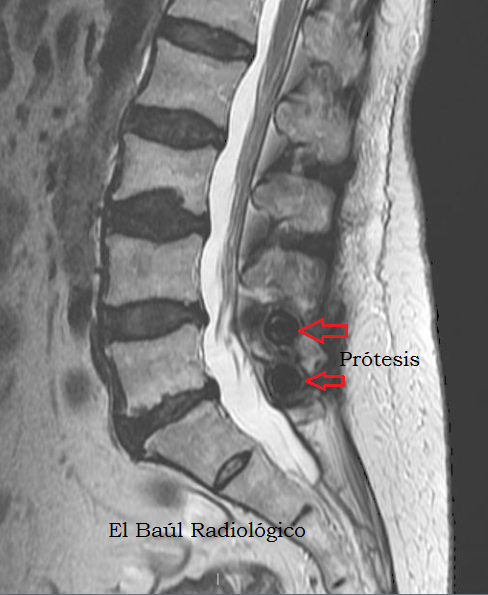

Hospital Universitario Miguel Servet (HUMS) Zaragoza. Spaiñ.

Ya hemos presentado algunos de estos implantes. Pero para que la colección sea completa añadimos algunas imágenes de uno de los más utilizados, los intersomáticos que se colocan en el espacio intervertebral. Es muy importante que los pacientes portadores de cualquier tipo de implante, lleven con ellos el informe quirúrgico donde se indique con precisión, el modelo que llevan y el nombre comercial exacto, para enseñarlos cuando vayan a realizarse una exploración de TRM. Es lo menos que se puede exigir, de lo contrario es posible que no les quieran realizar el examen por precaución y tengan que marcharse a su casa contrariados.

(In recent years, engineers have designed multiple biomedical implants to correct the physical damage suffered by the spinal column with the age. We have presented some of these implants. But the collection may be complete, we show now some pictures of one of the most used, the intersomatic implants that are placed into the intervertebral space. Figures 1-2).

FIGURA1) Componente metálico de un implante intersomático situado en la columna cervical, entre los cuerpos vertebrales (los somas) C5-C6.

(Metallic component of an intersomatic implant placed in the cervical spine, between the vertebral bodies (the somas) C5-C6).

Los implantes intersomáticos vertebrales  son de  aleaciones de titanio, y por ese motivo se pueden realizar exploraciones de Tomografía Computarizada y Tomografía por Resonancia Magnética sin ningún problema. Tampoco producen artefactos en las imágenes ni se calientan por el efecto del campo magnético del imán.  El implante tiene una forma ovalada o redonda y  se insertan fácilmente en el espacio intersomático por vía percutánea.

(Intersomatic vertebral implants are titanium alloy devices, and for that reason we can perform computed tomography and magnetic resonance imagin scans without any problem. Neither produce image artifacts or are heated by the effect of the magnetic field of the magnet)

Pr%C3%B3tesis+intersom%C3%A1tica+1.png

FIGURA 6)  En las exploraciones de TRM de columna los implantes se distinguen con mayor dificultad, como una zona oscura intervertebral. Más llamativas  son las bandas brillantes que se producen en el tejido esponjoso de las vértebras adyacentes,  por microfracturas trabeculares (flechas rojas).

(On MRI scans of the spine, the implants are distinguished with difficulty, as an intervertebral dark area. More striking is the finding of bright bands in the cancellous tissue of adjacent vertebrae, produced for trabecular microfractures (red arrows).